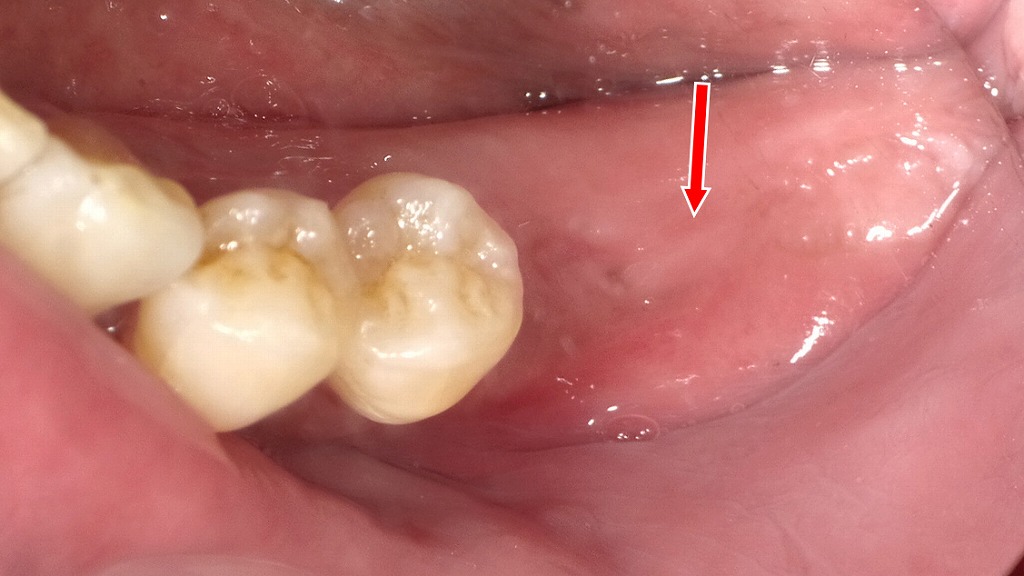

重度の歯周病などにより歯が大きく動揺し、保存が困難と判断された6番を抜歯した症例です。欠損部を放置すると噛み合わせの乱れや周囲歯への負担増加を招くため、抜歯後の治療としてインプラントを選択しました。2枚目の画像は、6番欠損部にインプラント体を埋入した状態を示しています。インプラントは、周囲の健康な歯を削ることなく、歯根の役割を回復し、しっかり噛める機能と咬合の安定を取り戻すことができる治療法です。

歯周病で歯がグラグラした時の暫間固定です。

審美的に治療する必要がある前歯では歯と同じ色の接着性レジンで固定します。

奥歯では審美的要求が低いことと咬合力が強いため、ワイヤーで補強し外れにくくします。